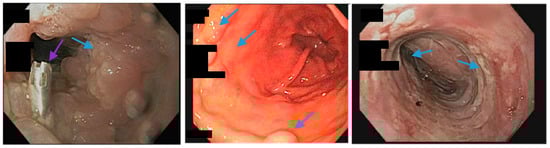

Upper endoscopy reveals an inflammatory mucosal reaction (blue arrows; left, middle and right) following the removal of a partially covered, esophageal self-expandable metal stent used for the treatment of a staple line leak in a patient with a sleeve gastrectomy. The patient reported severe regurgitation and chest pain associated with the stent. A through-the-scope clip (purple arrow, left) was used to anchor the removed stent.

Figure 1.

Upper gastrointestinal series reveals a 23 mm × 15 cm fully-covered esophageal self-expanding metal stent from the distal esophagus to the mid portion of the sleeve anchored by two through-the-scope clips (blue arrows) and one over-the-scope clip (green arrow) placed on the proximal edge of the stent.

Scheme 6.

Upper endoscopy reveals the proximal (blue arrows, left) and distal edge (blue arrows, middle) of a fully-covered esophageal self-expanding metal stent anchored by two through-the-scope clips (blue arrows, right) and an over-the-scope clip (green arrows, right). Note copious saliva collected around the non-peristaltic prosthesis.

Figure 2.

Upper endoscopy reveals the use of a suturing system (arrow, blue) with a suture in place (arrow, green) at the leak site in a patient following sleeve gastrectomy.